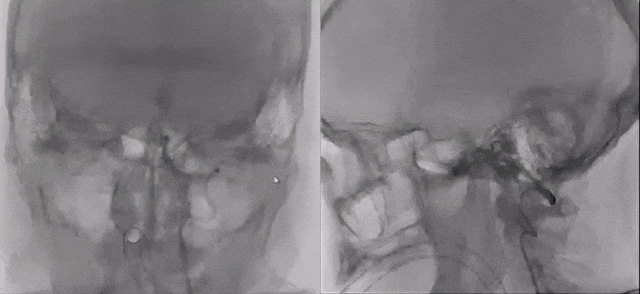

点击上方图片,查看手术详细视频